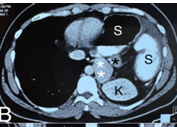

Congenital diaphragmatic hernia (CDH) is a birth defect involving improper formation of the diaphragm, leading to the protrusion of abdominal organs into the chest cavity. The CDH is classified depending on the location of the defect as postero-lateral, central and anterior. Depending on the side, it is classified as right, left and bilateral. A majority of CDH defects are postero-lateral defects and are commonly referred to as Bochdalek hernias (BH). Herein, the authors present the case of a 29 years old male patient diagnosed with a large left recurrent Bochdalek hernia. He was operated for it in another hospital by another surgeon 5 months back. That previous surgical intervention was initially planned via laparoscopy. But, intraoperatively, it had to be converted to open surgery due to technical difficulty. Post the first surgery, after about 1.5 months, he started developing pain in the back of his left chest. However, due to financial constraints, he did not seek any consultation with anyone at that time. The authors successfully performed a laparoscopic repair of this difficult condition. The rationale for reporting this case is to underscore the relative ease of a laparoscopic over open surgical intervention, on the ‘roof’ of the abdomen and also the lower chest. Also, it hopes to highlight that laparoscopic repair of BH is feasible even in challenging, difficult and recurrent scenarios, in an advanced setup backed up by the requisite surgical expertise.